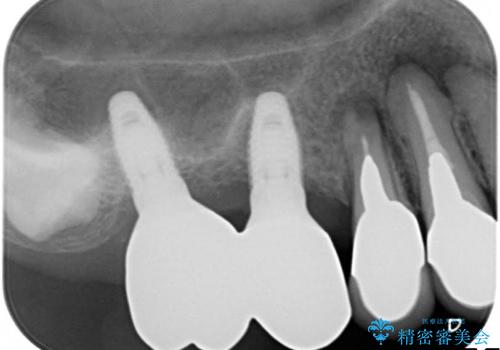

薄い骨にもインプラントを スプリットクレスト+ショートインプラントの応用

- 破折により保存不可能となった歯を抜歯後、待時してインプラントを計画した。

骨が薄く、インプラントの径に耐え得ないと判断したためスプリットクレストにより骨幅を拡大しインプラントを埋入した。

スプリットクレストやリッジエキスパンジョンといった方法は、骨が薄く、細い場合に、割線を設定し、狭い骨幅を拡大すると同時にインプラントを埋入することができます。

インプラントの種類:Bicon

かぶせ物の種類:PFZ